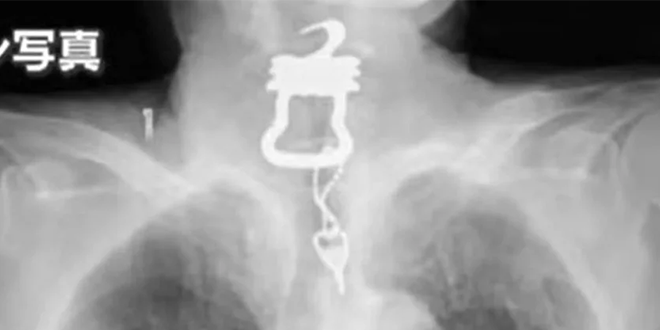

ورغم استقراره في البداية، إلا أن حالته تدهورت بعد عدة أشهر، حين اشتكى من آلام في الحلق، وتبين لاحقاً في صور الأشعة وجود “ظل كبير” في الحنجرة، ليتضح أنه مفتاح معدني ثقيل ذو أطراف حادة، كان موصولًا بسلسلة معدنية على شكل أوزة.

المفتاح لم يكن عادياً، بل هو جزء من “بدلة خاصة” يرتديها المرضى الذين يعانون من الخرف، وتُستخدم لتقييد الوصول إلى المعدات الطبية أو الحفاظ على الحفاضات، حسبما صرّح نجله البالغ من العمر 55 عاماً.

وقد عبّر الابن عن صدمته الشديدة عند رؤية المفتاح الحقيقي، قائلاً: “تخيلت في البداية أنه مفتاح صغير ابتلعه عن طريق الخطأ، لكن ما رأيته كان ثقيلًا وغريب الشكل.. لا يسعني سوى التفكير بكمّ الألم الذي تحمله والدي”.